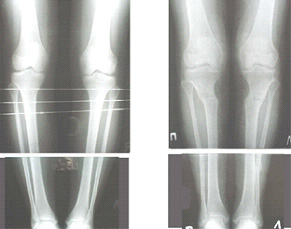

Re: Деформация голеней

Alexander Chelnokov 13 Сентябрь 2005, 23:23

Как уже писал, вчера сделал одну ногу (может, свой плюс будет что не обе- вдвое меньше травма, сразу на костыли встанет, оперированную ножку немного разомнет, тут и вторую заделаем).

Операция была интересной, много полезного опыта приобрел.

Снимки в приложении - фас сравнительный с неоперированной ногой. Жду критики.

Впрос про остеотомию большеберцовой непраздный. Эта получилась при надломе несколько более наклонно, чем я делал (сейчас проблема,

как на второй ноге сделать так же). Вот этот высоящий "зуб" центрального отломка не заменит ли в плане косметики то, что получается при медиализации дистального?

|

Отправитель: T. Derek V. Cooke 14 Сентябрь 2005, 18:23

Hi Alex:

Nice job!

It is very interesting to me that as you have derotated the tibia you have centred the patella, I think and the prox tibia looks much more anatomic.

The analysis in the attached images is direct, just using the tools.

Tibial tilt is perhaps more than you want but the tibial correction is to 90 (very slight over

correction.

Will need full length views to tell us about the hka but it appears neutral.

Measurements took 4 mins

Derek